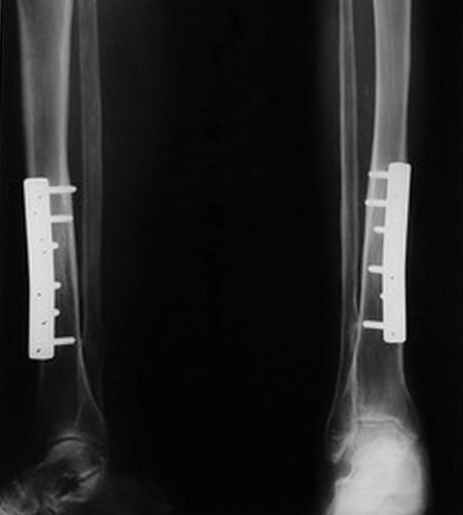

Поступила больная 68 лет с чрезвертельным переломом левого бедра. Все бы ничего, но на правой голени интересная картинка.

Со слов пациентки оперирована в 1997 году. После выписки из стационара нигде не наблюдалась. Данная картина уже 3 года. Пластинка появлялась постепенно после падения на оперированную конечность. На вопрос, почему не обратилась к врачу, ответила, что не посчитала нужным, хожу нормально, ничего не болит!